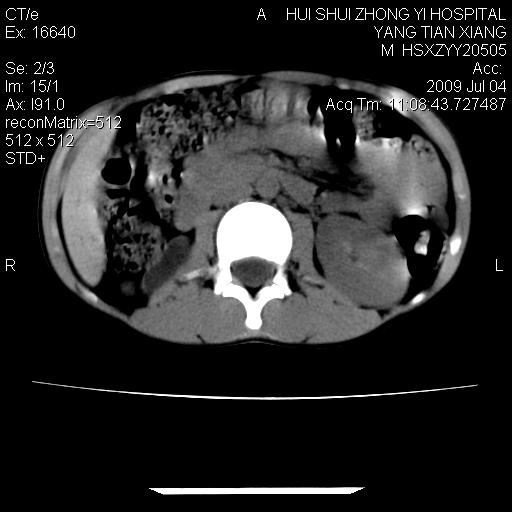

肝右叶胆管内见条状高密度影,脾脏增大,双肾上腺无异常;右肾正常结构消失,其实质内见类圆形低密度灶,ct值范围0-6hu,界清,右输尿管全程伴行多发低密度灶,界清,膀胱壁增厚,腹盆腔未见确切肿大淋巴结。

考虑:1、肝内多发胆管结石并肝内胆管扩张。2、右肾、输尿管多发脂肪瘤,多发平滑肌瘤?建议ct增强检查。4、膀胱壁增厚。

1)考虑右侧巨输尿管畸形。2)肝内胆管多发性结石。3)脾大。

右侧巨输尿管并神谕积水,左肾代偿性肥大,脾大,肝内胆管多发结石并胆管扩张。